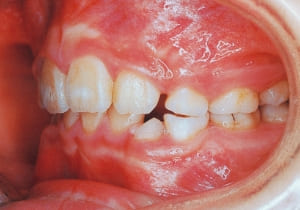

1 Initial Visit 2-11-’88

3 Initial Visit 2-11-’88

4 Initial Visit 2-11-’88

The Class II condition is pronounced, with a significant overjet of 12.5 mm(3). Although the teeth size are large, crowding is relatively mild. The maxillofacial structure has good depth and a robust bone framework(5). The mandible itself is solid , robust gonial angle, but there is significant anterior-posterior displacement relative to the maxilla(ANB 10.0°). While there is no confirmed history of thumb-sucking or similar habits, the lower lip is already pushing up against the maxillary incisors. The cause of this condition is unknown.